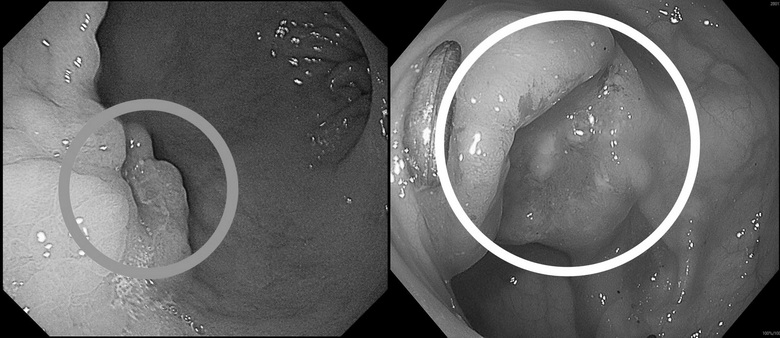

圖說2:病人接受詳細檢查,醫師在其胃部及乙狀結腸內均發現癌灶(圓圈處)。圖/高醫岡山醫院提供

收治病人的高醫岡山醫院一般及消化系外科主任吳柏宣表示,張先生因突發上腹悶痛、糞便顏色變黑,由家人陪同到急診就醫。因懷疑有消化道出血,安排胃鏡檢查,在胃部發現兩公分惡性腫瘤,進一步做大腸鏡檢查,確認乙狀結腸也有一處3公分腫瘤,所幸兩處皆為可手術根治之病灶。